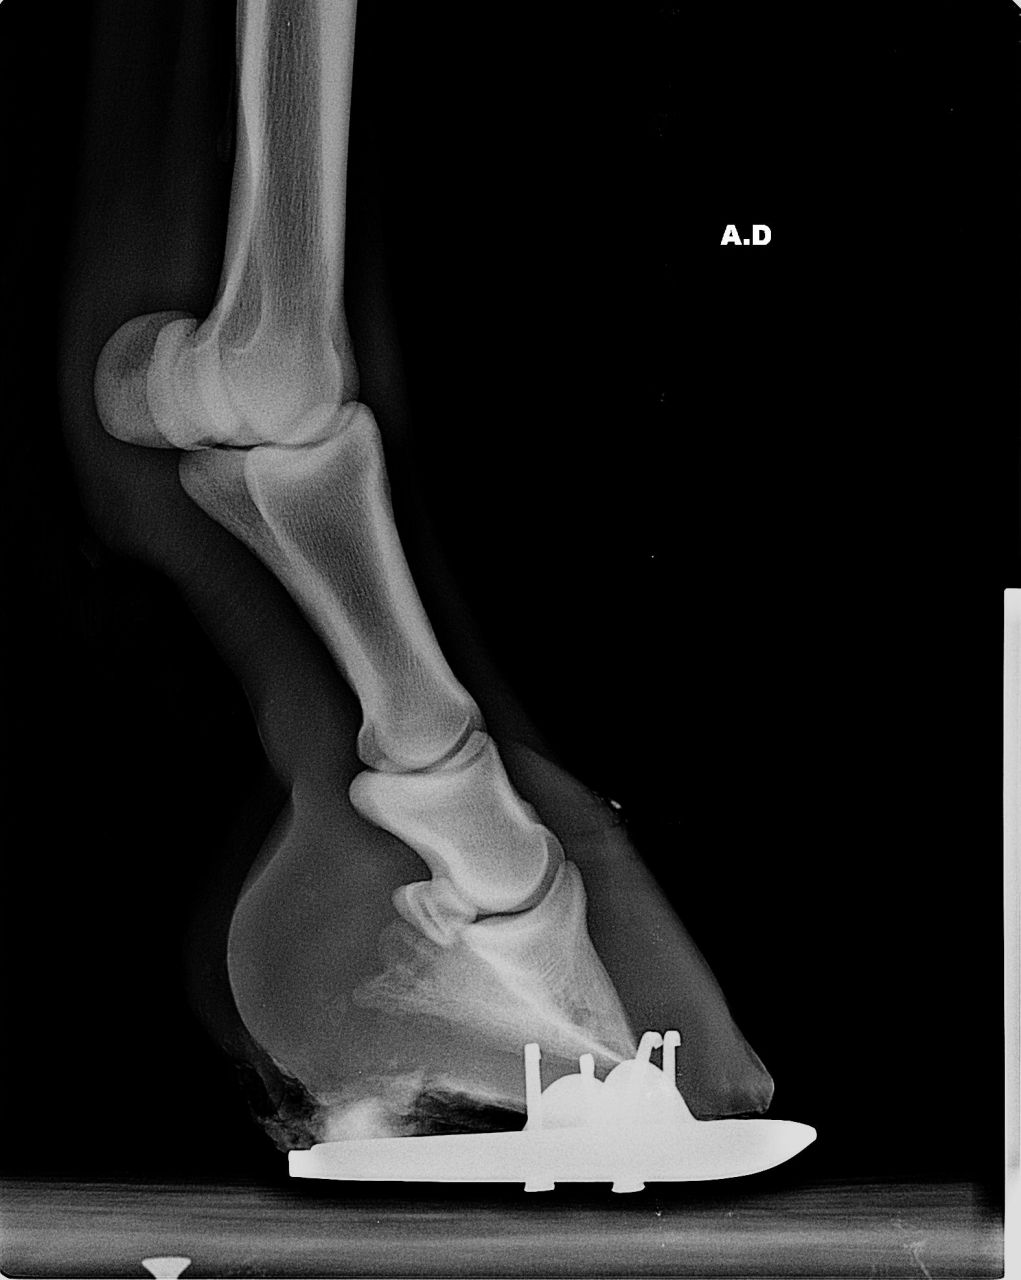

| Dire merci | bonjour je vous présente Quizzy, ponette ONC de 7 ans. ![]() nous l'avons achetée il y a deux ans, débourrée, travaillée. malheureusement, Quizzy est fourbue depuis 5 semaines. 1ers veto et MF, une catastrophe. l'état de quizzy s'est dégradé. j'ai fait appel à un autre veto (pas celui du club) spécialisé et un autre MF. on a fait des radios. bascule très importante de la 3ème phalange aux antérieures (beaucoup plus "légère" sur les postérieurs) ![]() aujourd'hui, quizzy est au box, au foin. c'est dur pour elle qui vivait au pré (je précise qu'il ne s'agit pas d'une fourbure due à l'obésité... elle ne l'était pas... mais plutot d'une fourbure d'effort/exces d'eau froide). pour nous, c'est dur aussi. car on veut y croire et tout faire pour elle mais on n'entend que des "mais elle est foutue, pourquoi tu t'emmerdes", "à ce degré de basculement, plus rien à faire", "tu pourras plus la monter", "t'es dingue d'engager des frais" etc... alors, comme j'ai besoin d'un peu de soutien moral, je fais ce post, pour parler des, je l'espère, progres de quizzy, que nous aimons et pour laquelle nous voulons nous battre. si, parmi vous, certains ont eu des cas de basculemements importants avec issue "positive", les témoignages seront les bienvenus... voila, merci de m'avoir lue.... |

| Dire merci | voilà une radio d'un antérieur....pour vous donner une idée de la bascule (me suis trompée sur le premier post, j'ai mis un postérieur)![]() |

| Dire merci | je sais que la bascule est vraiment grave. pas loin de 20 degrés. .... mais c'est notre ponette et on l'aime. alors que faire ? la condamner de suite ? ou essayer et se battre pour qu'au moins elle puisse retrouver une vie correcte, au pré... c'est vrai que quand je la vois, là, qui après 5 semaines, a vraiment du mal à marcher et se déplacer.... ça fait putain de mal et on se pose des questions... mais là, hier, un nouveau MF est venu. il est très connu dans la région pour tout ce qui est difficile et orthopédique. et j'ai l'impression qu'elle se déplace un peu mieux.... et en plus, faut veiller à son moral. et moi, je suis pas sur place, c'est difficile. je cherche et cherche la meilleure solution.... c'est pour ça que ça me fait du bien d'en parler avec vous car c'est un très très long combat, je le sais bien |

| Dire merci | en plus de la bascule on observe un effondrement des phalanges dans le pied. ![]() Il faudrait abaisser les talons pour que le pied se pose plus à plat qu'en pince. ![]() Et puis courage les troisièmes phalanges semblent saines, non nécrosées. ![]() |